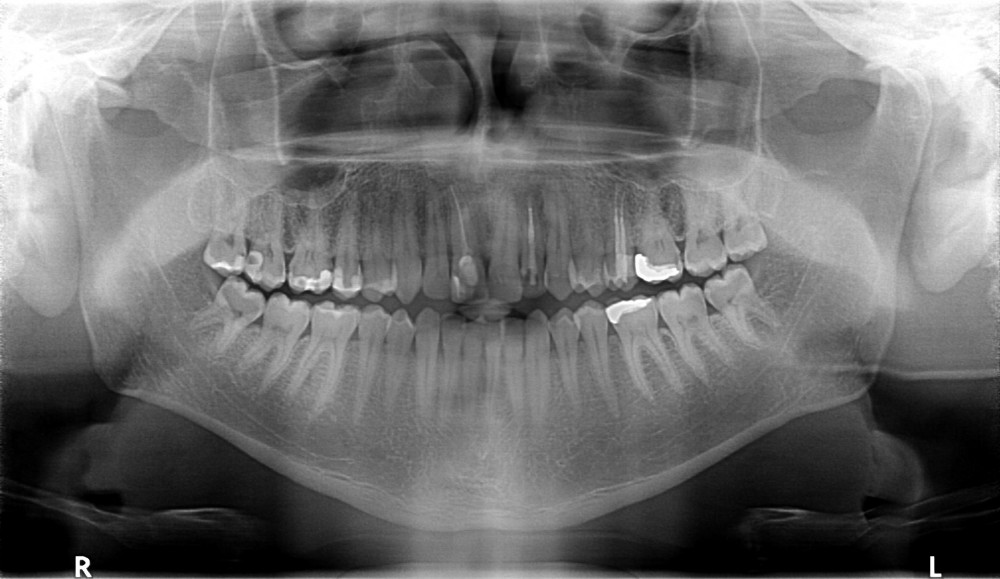

Przykład ekstruzji ortodontycznej za pomocą płytki termoformowalnej i zameczka ortodontycznego: